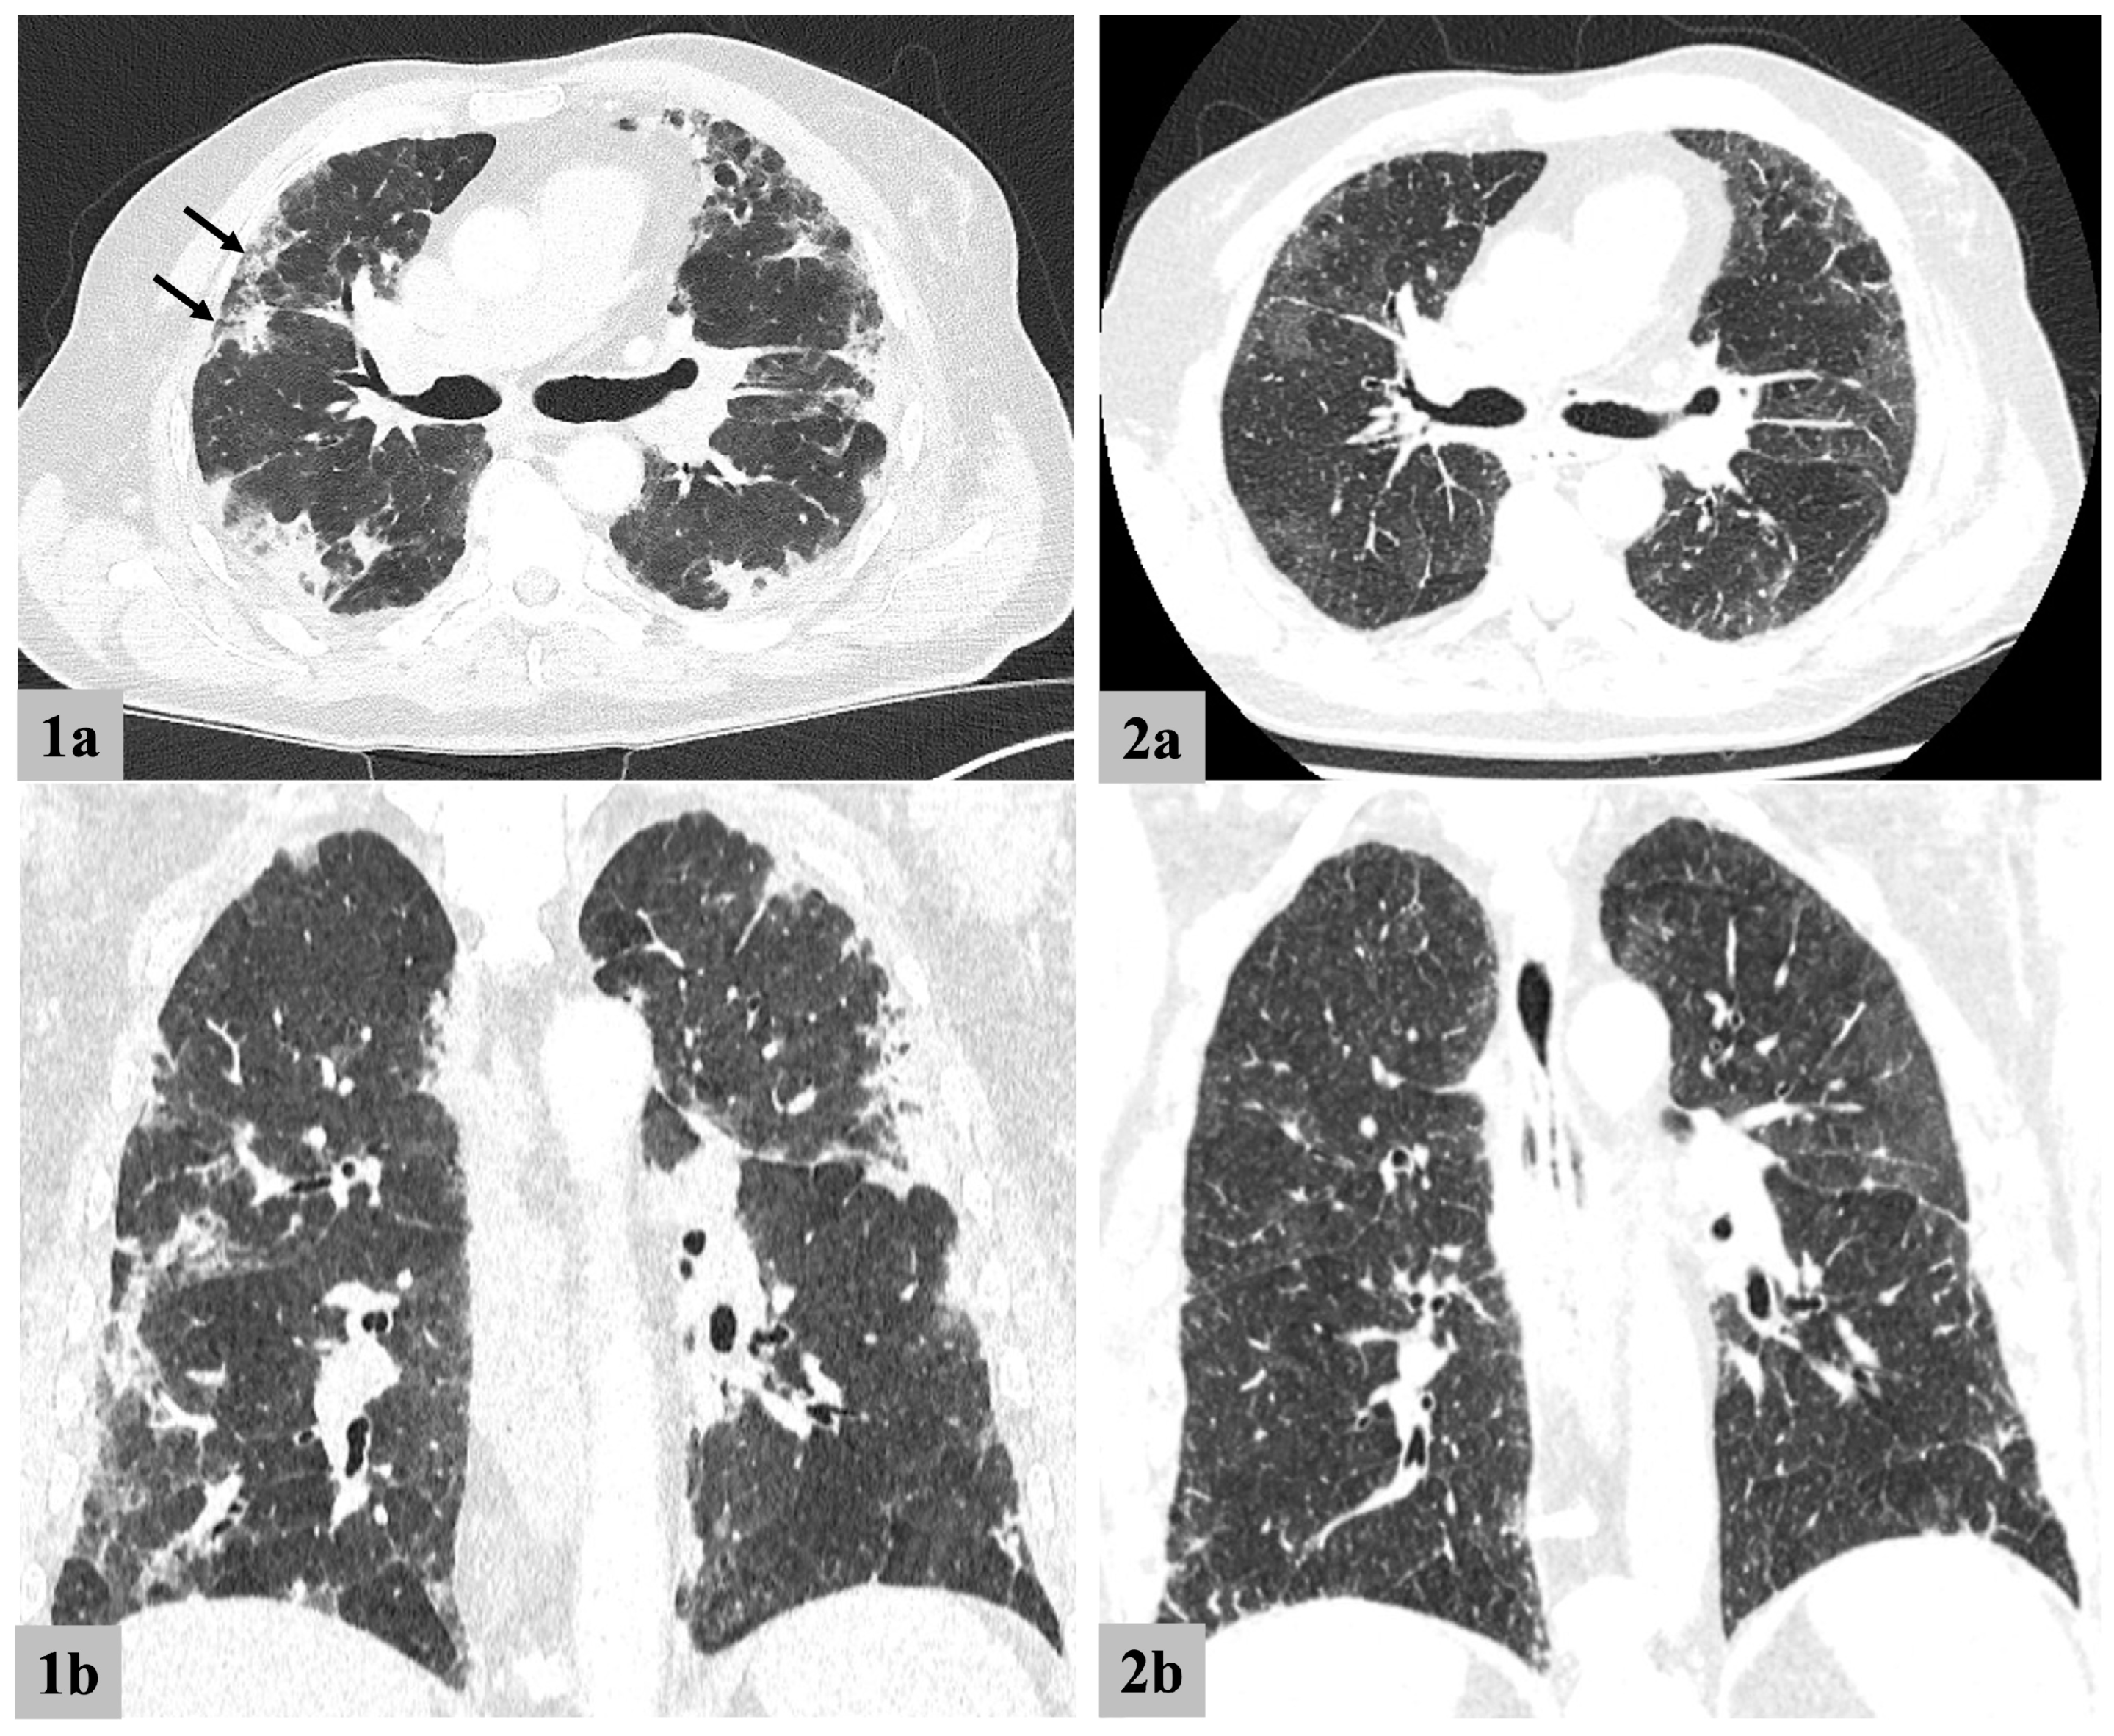

3.2.1. Chest